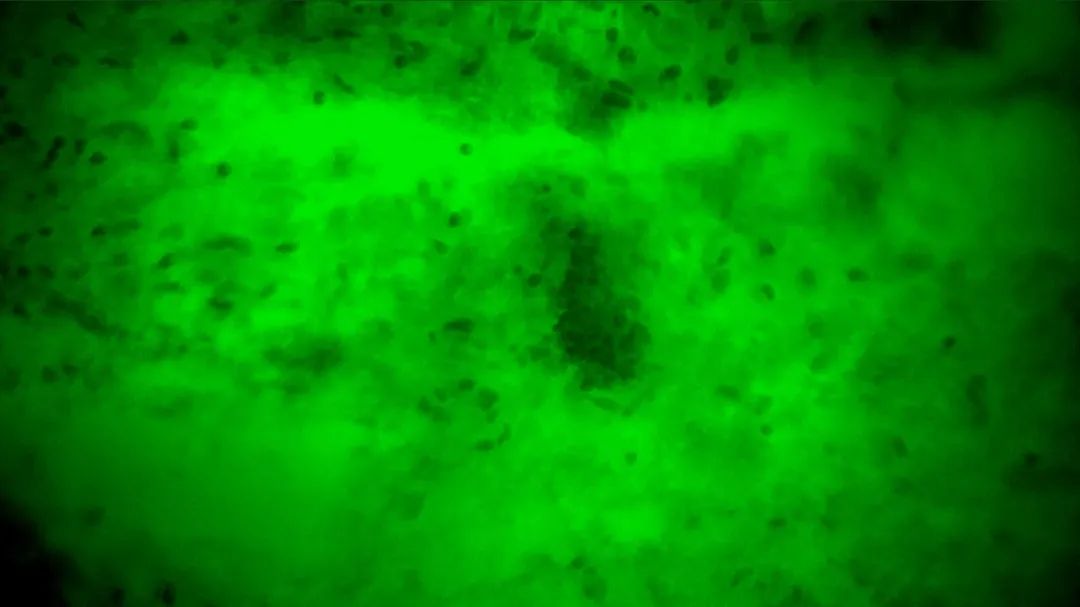

3次切緣掃查的EndoSCell?細(xì)胞圖像

1

陽性,細(xì)胞核異型、密集、分布不均勻